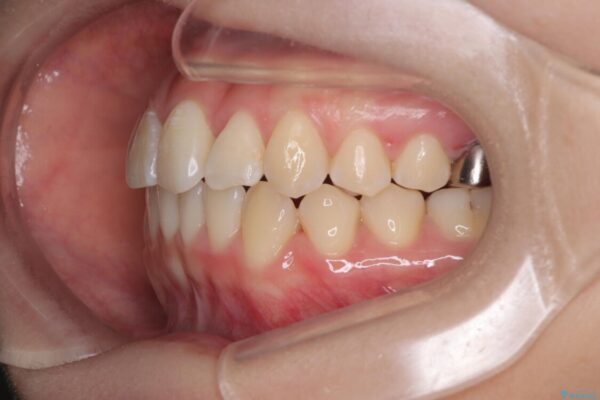

治療途中

• 前歯のねじれ・ガタガタを10か月で改善!20代女性の矯正治療|クリアブラケットでむし歯になりにくい歯並びへ改善 治療途中画像